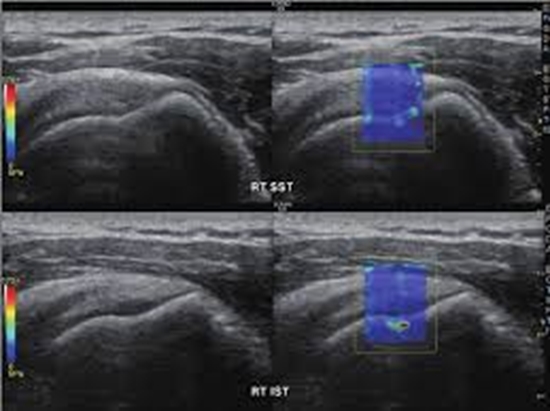

بررسی یافته‌های سونوگرافی و سونوالاستوگرافی shear wave تاندون اشیل در بیماران مبتلا به اسپندیلوآرتروپاتی سرونگاتیو و تعیین ارتباط یافته‌ها با فعالیت بیماری در بیماران مراجعه کننده به درمانگاه روماتولوژی بیمارستان شریعتی